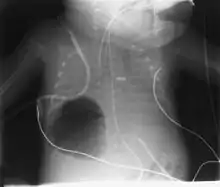

Diagnosis can be made using chest X-ray; the lesion shows up as a small, round area filled with air.[1] Computed tomography can give a more detailed understanding of the lesion.[1] Differential diagnoses – other conditions that could cause similar symptoms as pneumatocele include lung cancer, tuberculosis,[7] and a lung abscess[1] in the setting of hyper IgE syndrome (aka Job's syndrome) or on its own, often caused by Staphylococcus aureus infection during cystic fibrosis.